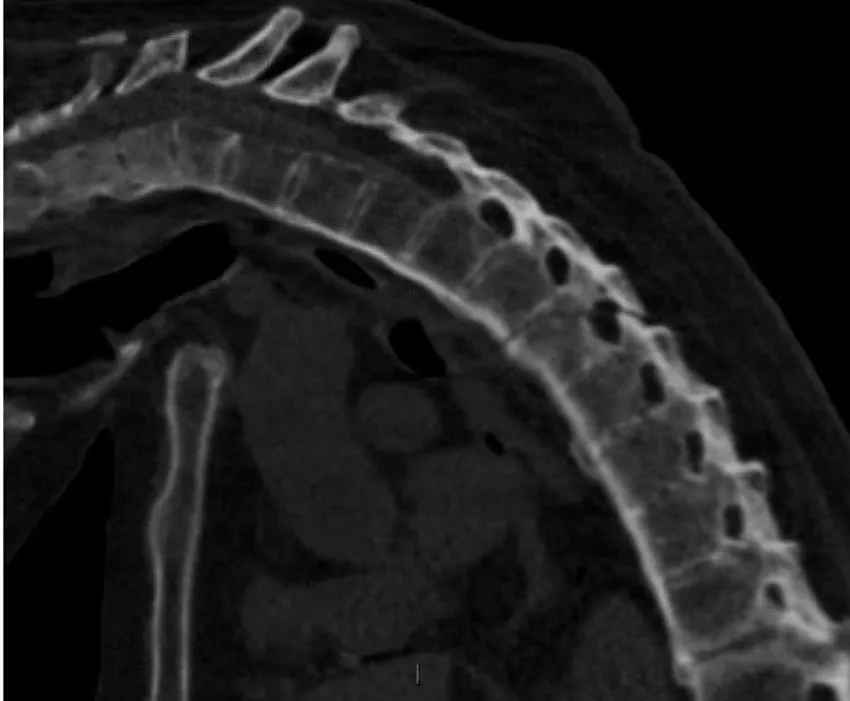

Images in exam case: Plain radiograph (4), CT (2) | |

- 2. CT whole spine:

- a. Ossification of anterior longitudinal ligament

- b. Fusion of multiple facet joints

- c. Severe cervicothoracic kyphosis

- d. Fracture line starting at D5/6 intervertebral disc and extending into the posterosuperior body of D6 and D6/7 facet joints

- e. Mild retrolisthesis of D5 over D6

- f. Widened lucent line through D10/11 disc space and facet joints with adjacent reactive sclerosis

DIAGNOSIS

- 1. Ankylosing spondylitis, acute fracture through D5/6 extending through the posterior elements. This is an unstable fracture as all three vertebral columns are disrupted.

- 2. Pseudoarthrosis D10/11, most likely secondary to non-union of an old fracture.

- 1. Urgent neurosurgical referral, as the fracture is unstable.

- 2. If there are signs of cord compression, MRI may be necessary to look for cord injury or spinal extra-axial haematoma.

Ankylosing spondylitis is a regular feature of the FRCR 2B examination, either as a written case or in the viva. The scenarios involved could be bilateral symmetrical sacroiliac joint erosion, sclerosis or fusion, erosion of the anterosuperior corner of the vertebra on lateral radiograph (Romanus sign), sclerosis of the anterosuperior corner and periostitis of the waist giving rise to vertebral ‘squaring’, syndesmophyte formation leading to ‘bamboo spine’, intervertebral disc calcification, ossification of the anterior longitudinal, posterior longitudinal, interspinous and supraspinous ligaments, kyphosis and facet joint fusion. Other skeletal features include erosions of the symphysis pubis and ischial tuberosities, asymmetrical erosive oligoarthritis, atlanto-axial dislocation and osteoporosis. In a traumatic setting, the fracture line may run through the intervertebral disc space right through into the posterior elements, and may be missed if one is not vigilant. Clinically occult fractures can also occur, leading to mobile non-union (pseudoarthrosis) – the so-called Anderson lesion.